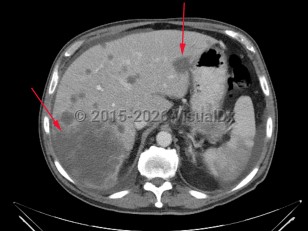

Hypersplenism

Liver cirrhosis

Liver cancerLiver cancer